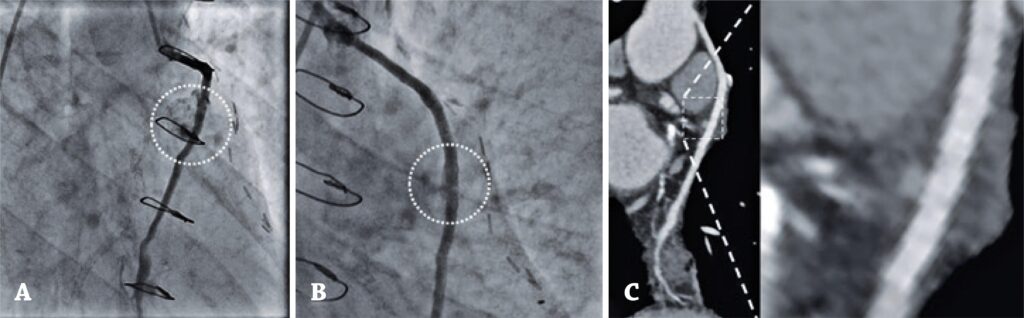

Figura 1

(A) Angiografia de enxerto de veia safena realizada em 2020 com pseudoaneurisma (sinal pontilhado). (B) Resultado da intervenção coronária percutânea de enxerto de veia safena para a artéria marginal, realizada em 2015, mostrando sinal de perfuração tipo I de Ellis (sinal pontilhado). (C) Confirmação por tomografia coronariana das imagens angiográficas (sinal pontilhado).